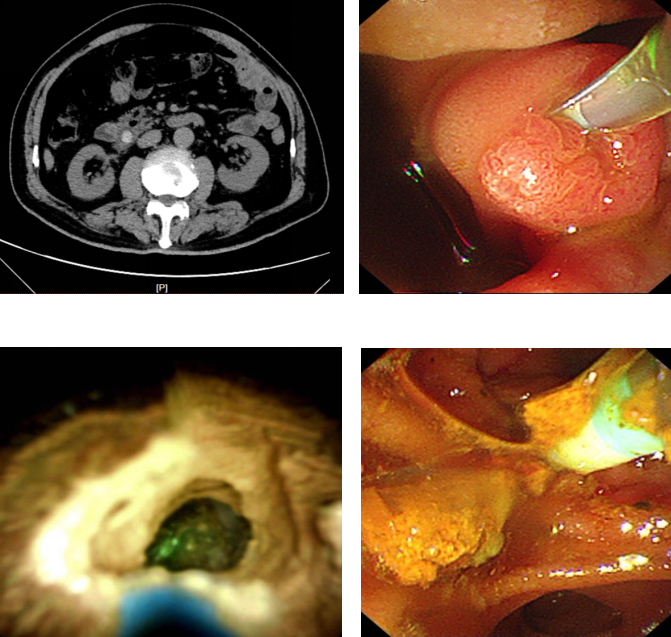

(荔枝新闻讯 通讯员/程倩敏)近日,75岁的马先生(化姓)因饮酒后突发剧烈呕吐,检查发现胆总管结石堵塞引发急性化脓性胆管炎,同时合并胰腺炎,病情危急。东南大学附属中大医院消化内科主任冯亚东主任医师团队紧急实施微创手术,运用该院在江苏省内率先开展的数字胆道镜辅助无射线内镜逆行胰胆管造影术(ERCP)治疗胆管结石,通过十二指肠镜,借助先进的胆道子镜系统精确定位结石,采用钬激光将结石粉碎取出,并植入支架疏通胆道。术后第二天马先生即可进食,五天后顺利康复。“从发病开始痛苦万分,到深夜急诊,以及迅速精细的微创手术,中大医院消化内科的医生护士们用专业和温暖创造了生命奇迹!”出院时,患者和家属无比激动地对医护人员说。

中大医院消化内科开展的这项先进的微创ERCP技术为何能让身处危情中的胆管结石患者得到快速的治疗和康复?据介绍,冯亚东主任医师团队最早于2019年在江苏省内率先开展了新型胆道镜直视下无射线ERCP微创手术,这种数字胆道镜的应用,可有效弥补传统ERCP的不足,其中单人经口胆道镜系统的运用较为成熟,其拥有双通道操作系统及高质量成像技术,可直接观察、定位和治疗胆管结石,同时可联合液电碎石和激光碎石等碎石技术治疗困难结石,为胆管结石的诊疗提供了新手段。